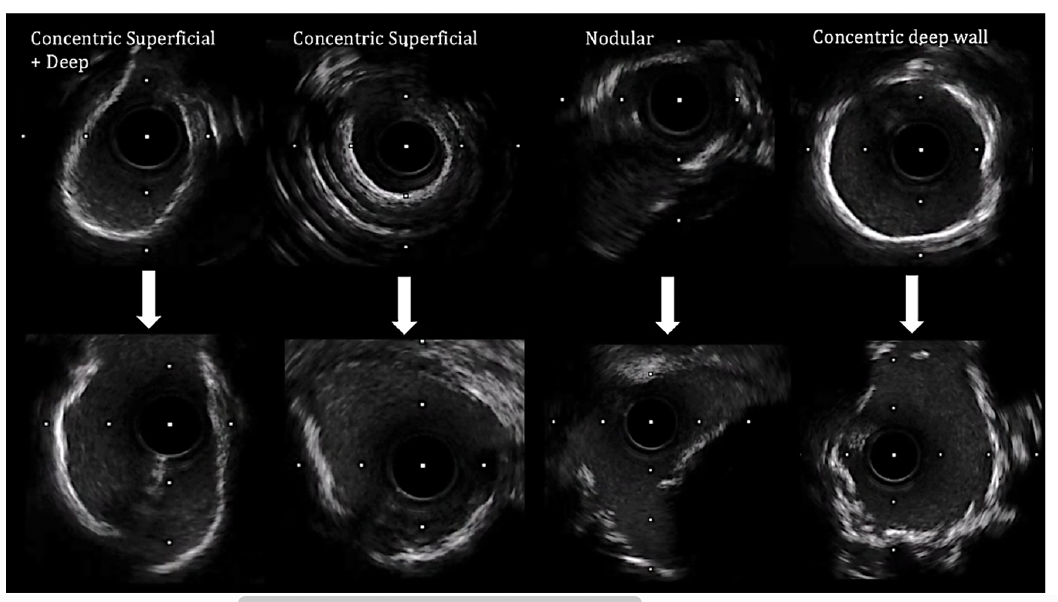

Intravascular ultrasound (IVUS) imaging (Figure 1B) showed all varieties of calcium throughout the LAD and LM. A 4.0 intravascular lithotripsy (IVL) balloon (Shockwave Medical) was used to modify calcium with the support of intracoronary phenylephrine to elevate baseline blood pressure prior to each 10-pulse delivery (20-30 pulses given) across the LM. This enabled modification without grossly compromising hemodynamics. A 3.5 mm x 48 mm Xience stent (Abbott Vascular) was deployed and optimized, with a final IVUS run showing good expansion and apposition. There was some eccentricity to stent expansion as expected with nodular calcium, but with a good area within the LM of more than 12.5 mm2. There was moderate disease in the circumflex that did worsen slightly after jailing with the stent. I briefly tried to cross, but with angulation and calcium, the support was not adequate.

Second, IVL is very helpful when treating vessels with a large lumen where severe calcium is present. We see this sometimes, where the lumen diameter may be 3 mm x 3 mm, bound by calcium in a vessel that is actually 5 mm. Here, a 2 mm RA burr is less likely to make an impact unless the wire bias is highly favorable, whilst IVL, if sized appropriately with imaging, we know will make contact with and modify the calcium in a more consistent and reliable manner (Figure 2). That doesn’t mean to say atherectomy doesn’t have a role: RA is crucial when you cannot cross a lesion or when there is significant intraluminal nodular calcium, where if wire bias is favorable and the lumen not too large, it can have a very good debulking effect. Not infrequently, both modalities can work synergistically to provide excellent modification and an optimal stent result. We are much earlier on the learning curve with orbital atherectomy (OA) in the U.K. than in the U.S., and I’m at the start of this journey, so have not had much personal experience yet with how OA may work to debulk nodular calcium in larger lumen vessels.